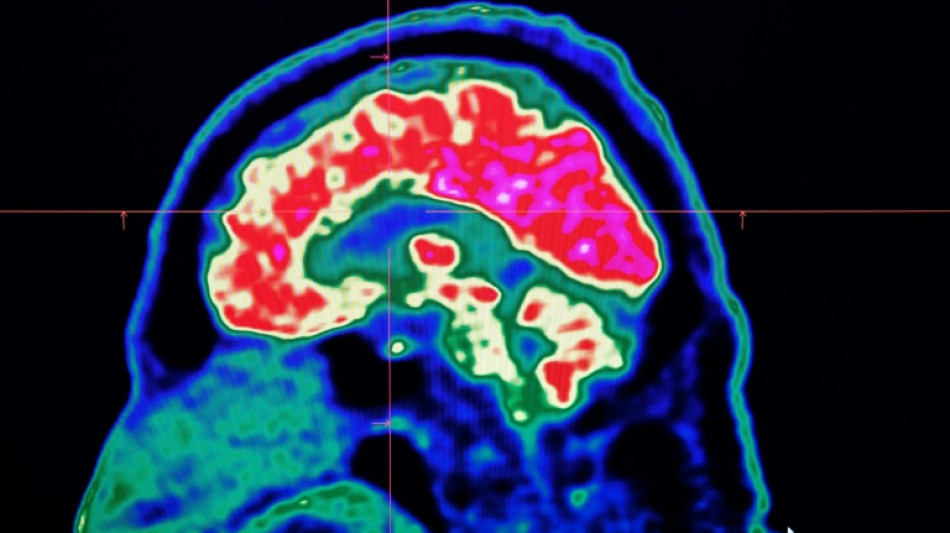

Surging nervous system disorders now top cause of illness: study / Photo: Fred TANNEAU - AFP/File

Conditions affecting the nervous system -- such as strokes, migraines and dementia -- have surged past heart disease to become the leading cause of ill health worldwide, a major new analysis said on Friday.